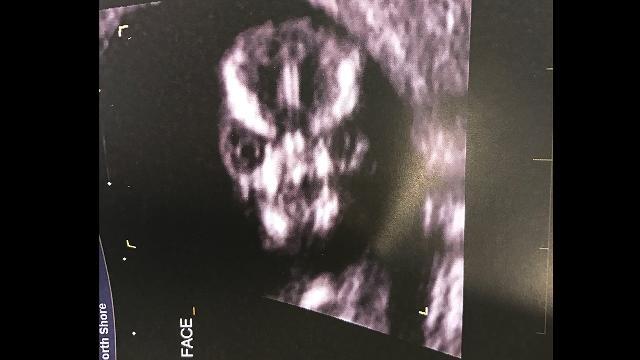

Doveva essere una semplice ecografia di controllo quella cui si è sottoposta qualche giorno fa Sharni Turner, una ragazza del Queensland. Dalle immagini, però, è emersa un’immagine assolutamente terrificante che ha fatto il giro del web